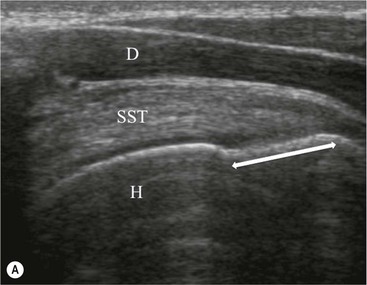

Radiography is useful for demonstrating bony abnormalities of the AC joint and acromion and excluding associated GHJ arthrosis (Fig. 46-1). Marked narrowing of the subacromial space is a specific but insensitive sign of a full thickness rotator cuff tear3 (Fig. 46-2). MRI and ultrasound (US) directly visualise the rotator cuff tendons. Both techniques are capable of diagnosing tendinopathy (Fig. 46-3), and have nearly 100% accuracy rates for FTTs of the rotator cuff.4 MR arthrography is not usually indicated for primary rotator cuff disease. The most important features to describe that help determine management include the following:

PTTs are less reliably demonstrated by both MRI and US, and it may be difficult to differentiate tendinopathy from partial tears. Focal clefts, tears, or tendon thinning affecting the articular margin of the footprint of the tuberosity are most common (Figs. 46-6 and 46-7). Tendon thickening is not always present. It is important not to mistake magic angle phenomenon on short TE MR sequences or anisotropy on US as evidence of tendinopathy.2